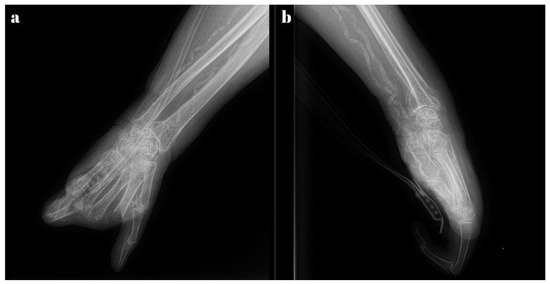

Among the subjective complaints, the most significant symptom was pain, characterized by its onset in an ischemic context. The radiological examination revealed an old malunited distal radius fracture, arthritic changes in the left wrist, osteoporosis, and calcifications in the walls of the radial and ulnar arteries (Figure 2).

Figure 2. Radiological exam—arteries with calcifications in calciphylaxis: (a) lateral view, and (b) anterior-posterior view.